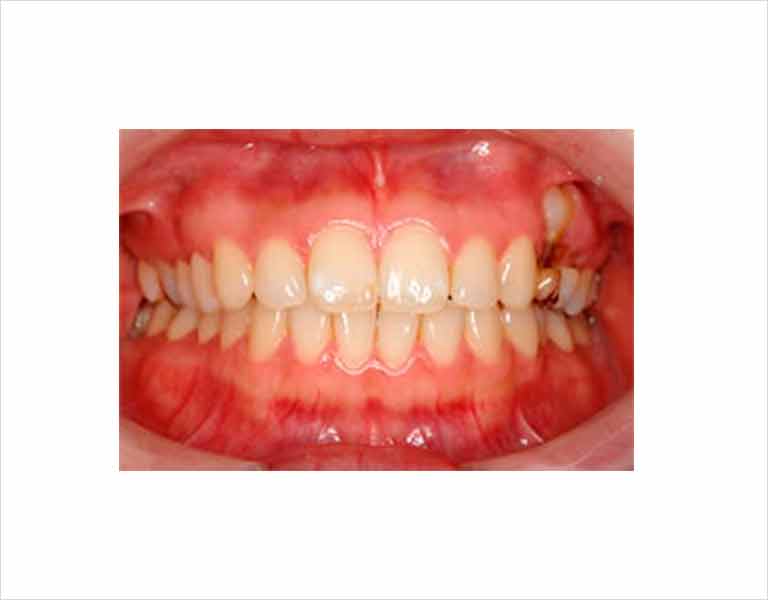

口腔内規格・写真の撮影

現状の分析と術前と術後の変化の記録のために、上半身、顔面、口腔内の状態を規格的に専用のデジタルカメラで撮影いたします。 撮影した写真を大型モニターを用いて映し出し、状況をご説明します。